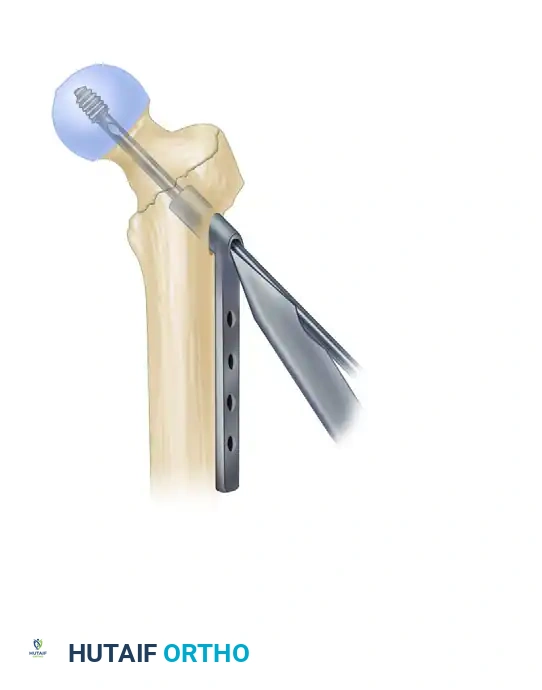

5. Lag Screw Placement and Compression

Achieving optimal lag screw placement is the most critical factor in preventing mechanical failure (cut-out). The goal is a Tip-Apex Distance (TAD) of less than 25 mm.

- Evaluate Version: Check the version of the nail on the lateral fluoroscopic view. The version is correct when the nail, the drill guide, the femoral neck, and the femoral head are all perfectly collinear.

- Make a small stab incision laterally through the skin and fascia lata corresponding to the targeting guide. Place the appropriate drill sleeve assembly down to the lateral cortex of the femur.

- Advance a threaded guide pin through the sleeve, up the femoral neck, and into the femoral head. Stop when the pin is within 5 mm of the subchondral bone.

- Confirm appropriate center-center position in the femoral head on both AP and lateral views.

- Measure for the length of the lag screw using the calibrated measuring device over the guide pin.

- Set the lag screw reamer to a depth 5 mm less than the measured length of the guide pin to prevent inadvertent joint penetration. Ream the lateral cortex and the lateral aspect of the femoral head.

- If the patient has dense, non-osteoporotic bone (e.g., a young patient with a high-energy mechanism), use a tap to prepare the thread path. In standard osteoporotic bone, tapping is generally unnecessary and may decrease screw purchase.

- Insert the lag screw over the guide pin until the threads are fully engaged in the subchondral bone of the femoral head.

- Use the centering sleeve insertion device to advance the centering sleeve over the lag screw shaft, locking it into the nail.

- Applying Compression: Before applying compression, release the traction on the fracture table. This allows the fracture fragments to settle. Insert the compression screw through the top of the nail and apply the desired amount of linear compression across the fracture site.